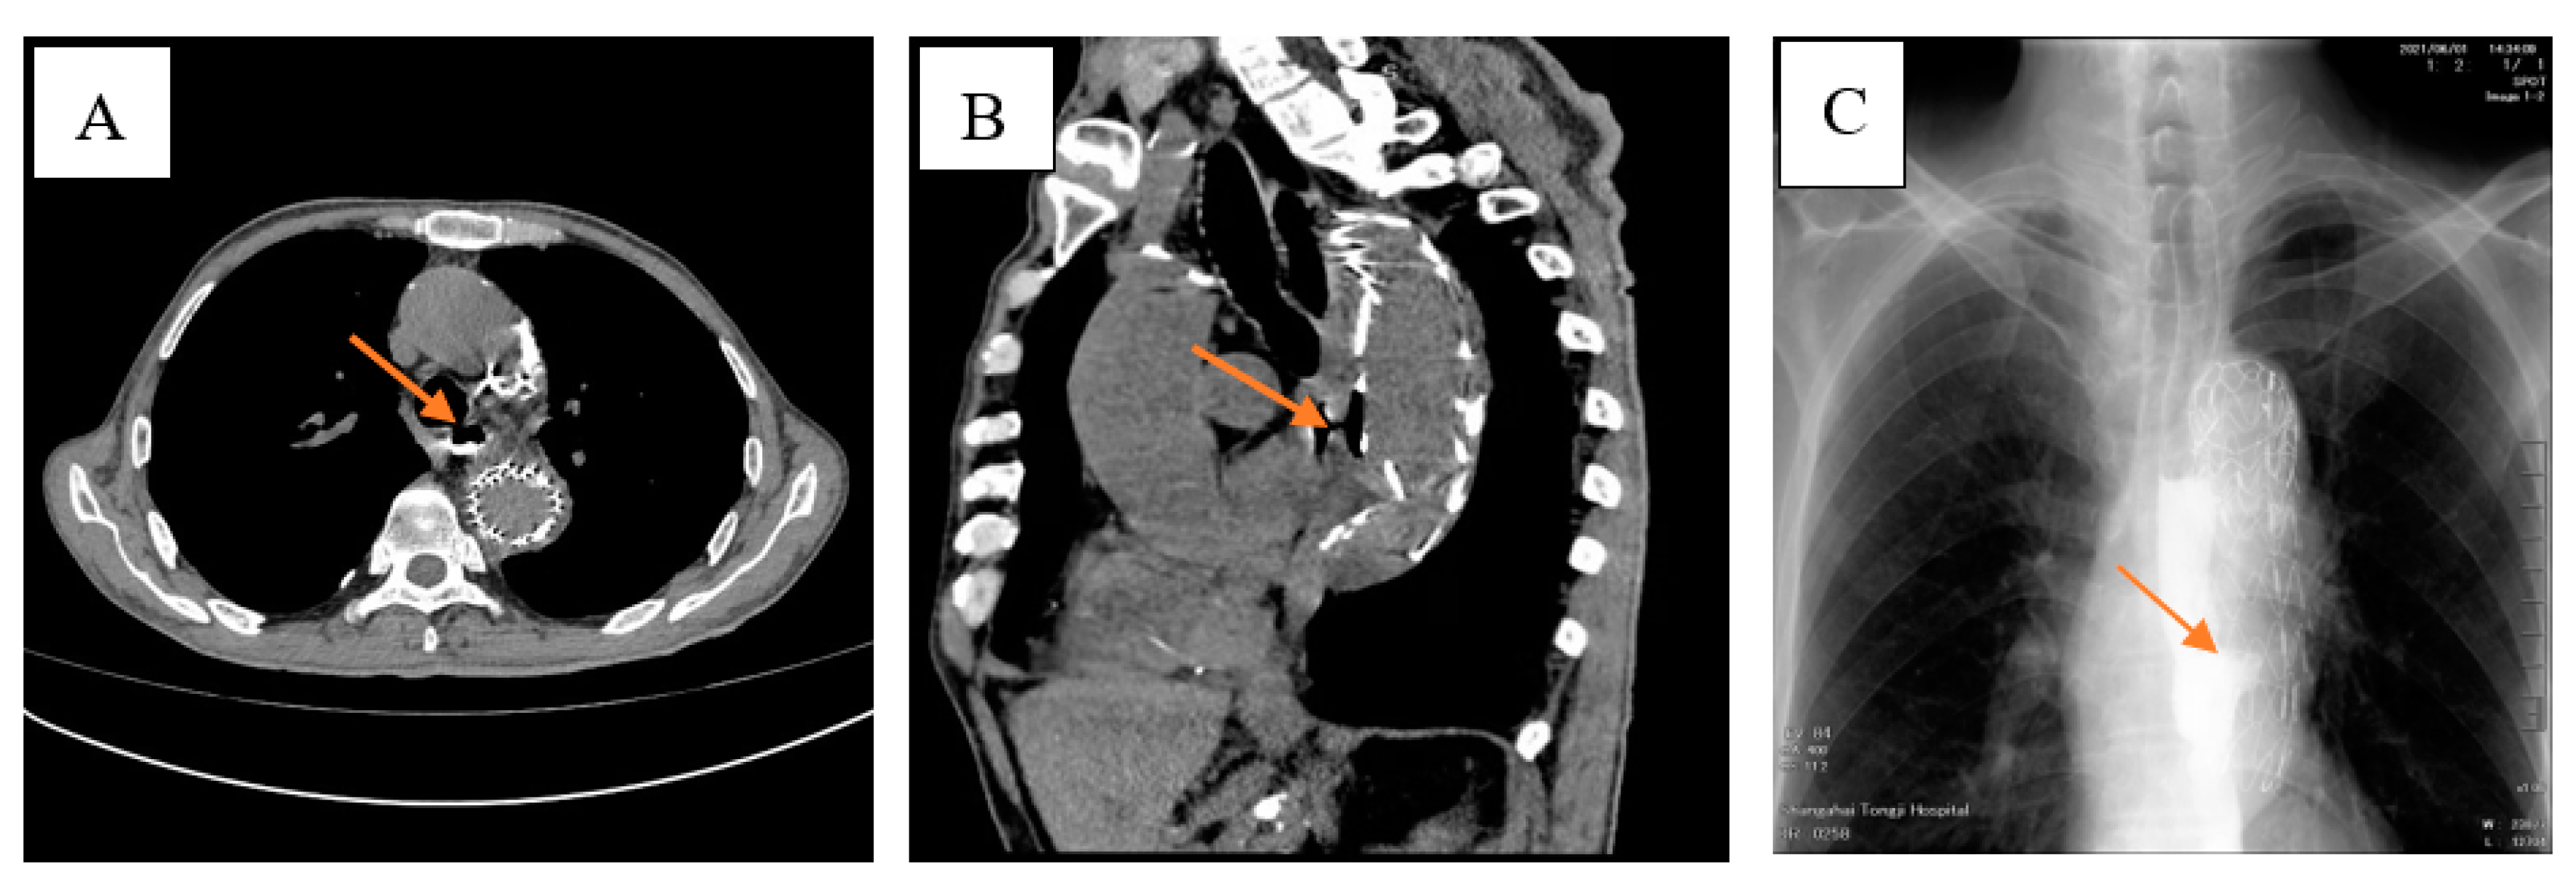

Aorticoesophagal Fistula Combined with Upper Gastrointestinal Bleeding after Endovascular Dissection of Thoracic Aortic Aneurysm